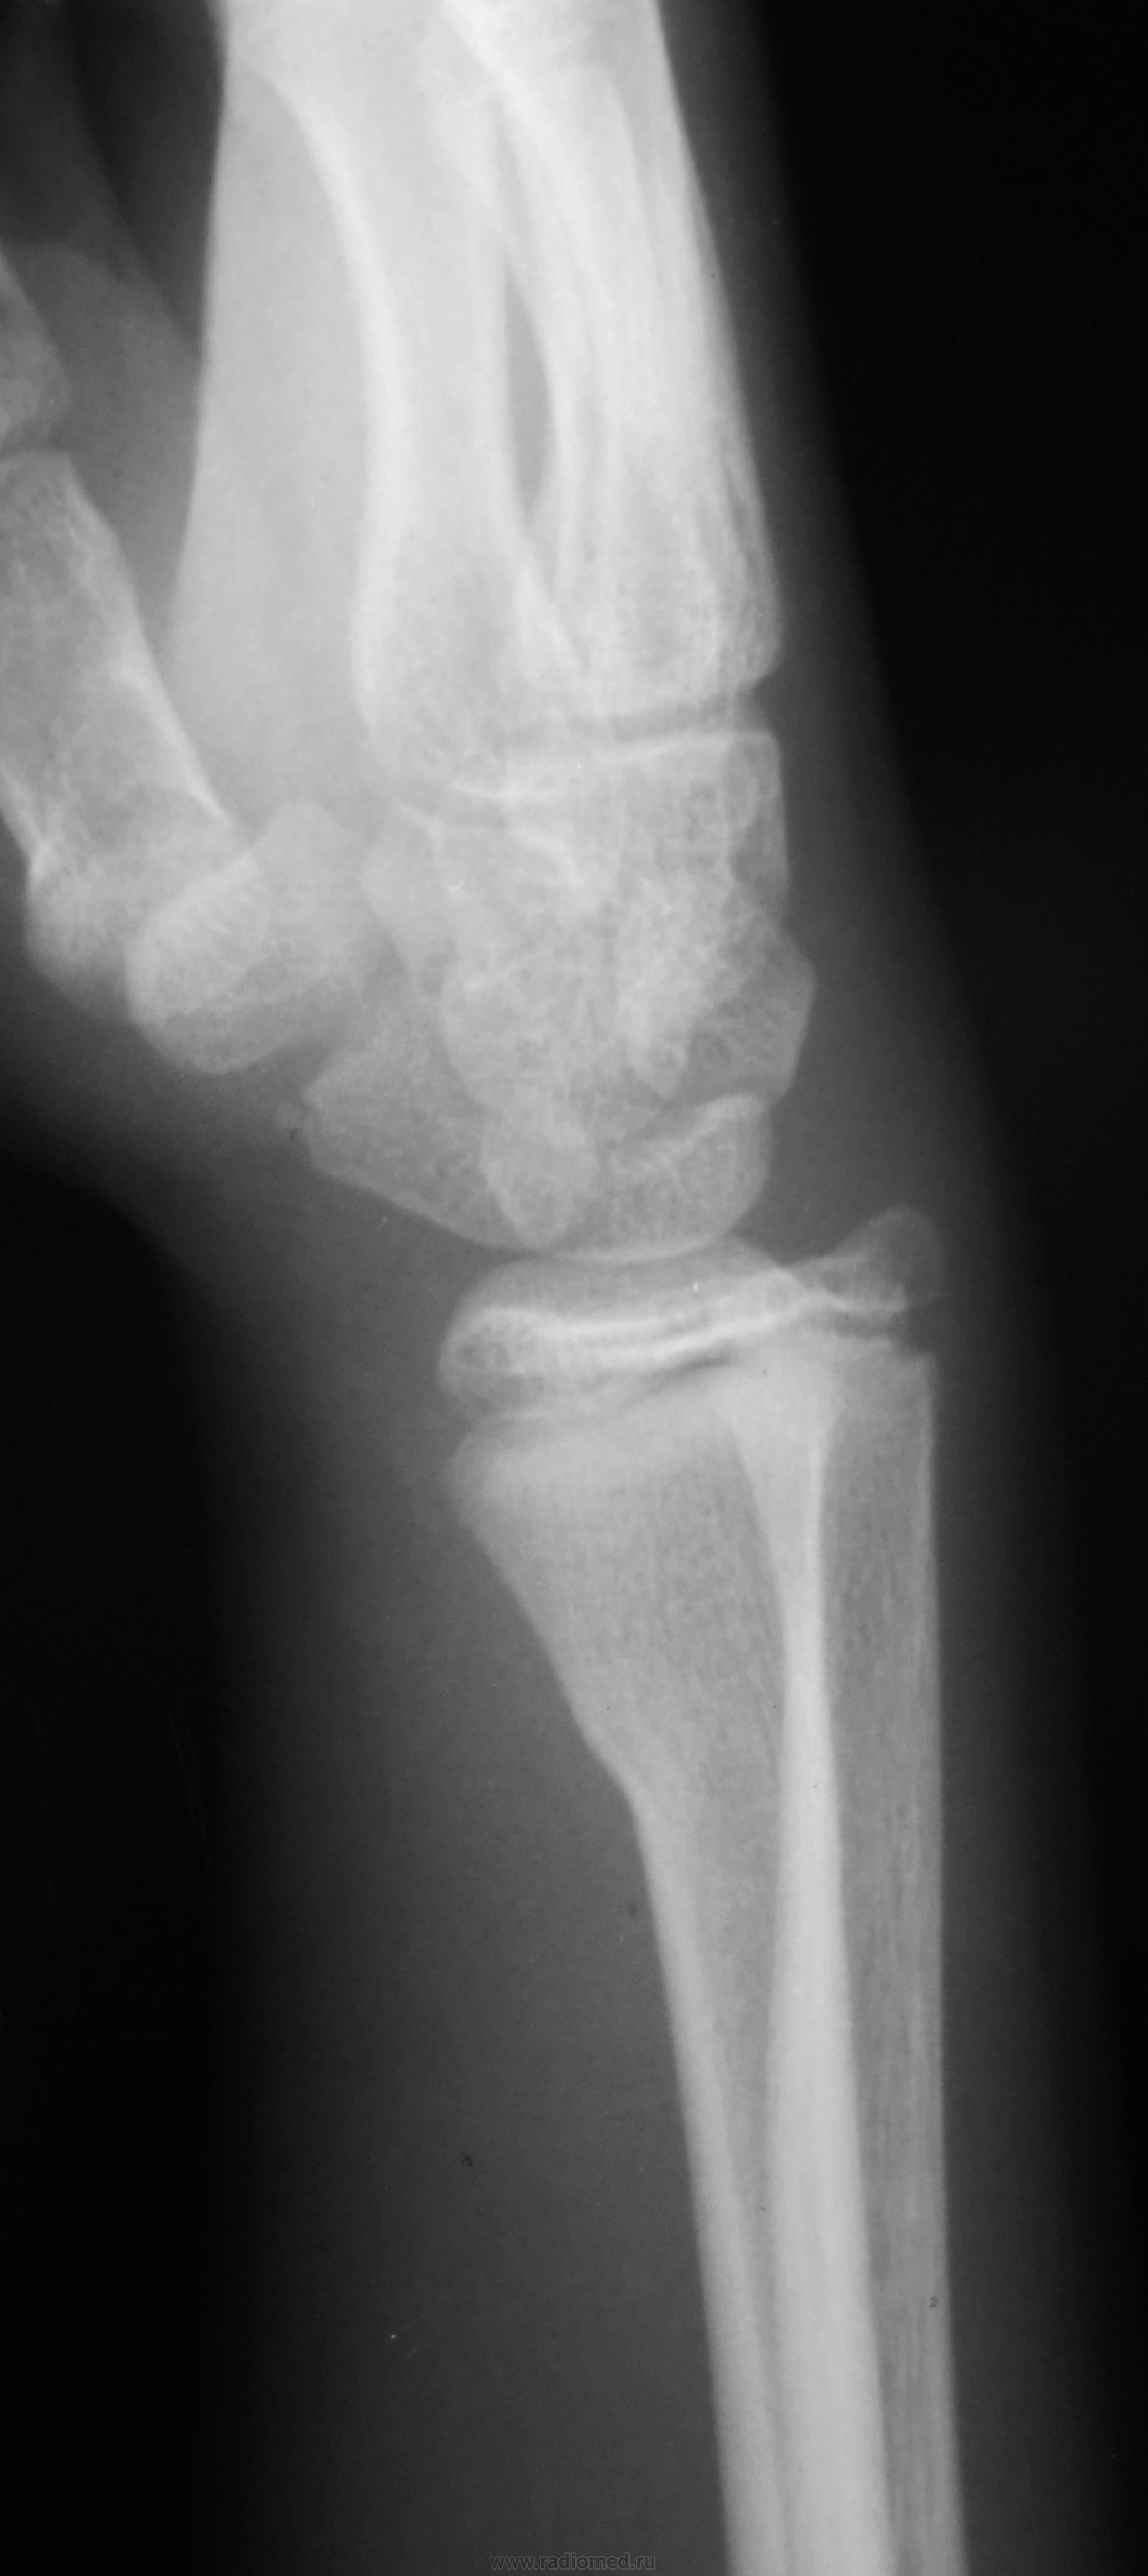

Травма. Пациент направлен на рентгенографию лучезапястного сустава

Осколок ладьевидной кости.

+ перелом дистального метафиза лучевой кости

поднадкостничный перелом дистального метадиафиза лучевой кости....без смещения отломков...ладьевидная кость так не ломается.)  сверхкомплектная кость...сочетать с клиникой ..с локализацией болезнености.

Поднадкостничный перелом лучевой кости в нижней трети без смещения. Краевой перелом ладьевидной кости? Остеохондропатия ладьевидной кости?

Гипсовый лонгет "на луч". Наблюдение в динамике, рентген-контроль по показаниям.